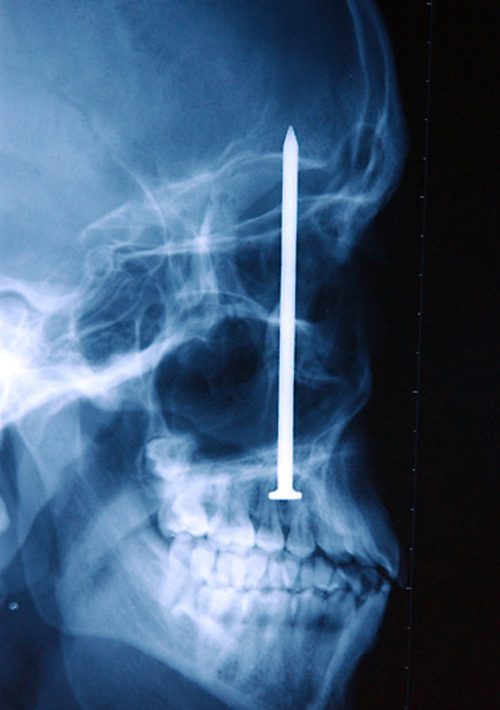

The skull of Chinese man who was shot in the head with a high-powered nail gun.

A nail embedded in the skull of a man after he accidentally shot himself with a nail gun. He didn’t even realize he had been shot until 6 days later when the four-inch nail was discovered.